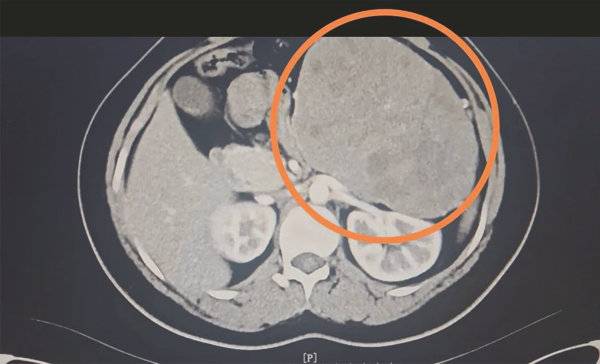

术前检查影像

患者为23岁青年女性,因“发现腹部肿物1月”入院,既往身体状况良好。患者术前CT考虑左上腹巨大占位,考虑胰腺肿瘤。MR检查提示胰腺体尾部占位,考虑胰腺实性假乳头状瘤伴出血,肿瘤体积巨大,如“西瓜”大小,直径约16cm。